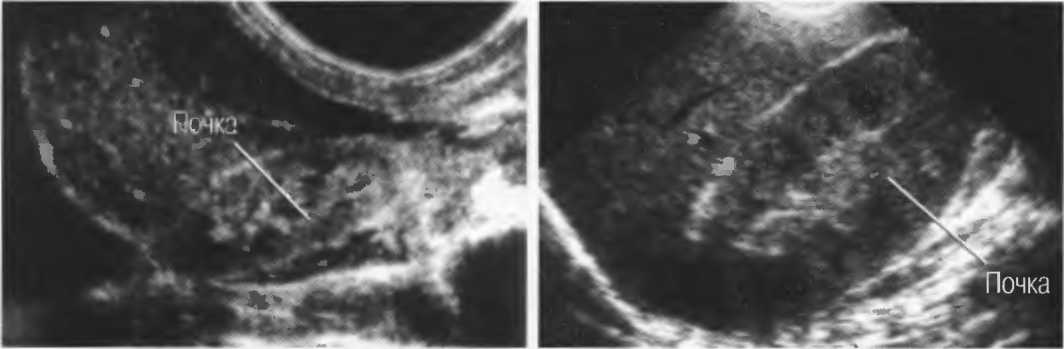

Диффузные изменения структуры синуса обеих почек

Диффузные изменения структуры синуса обеих почек 117 фото